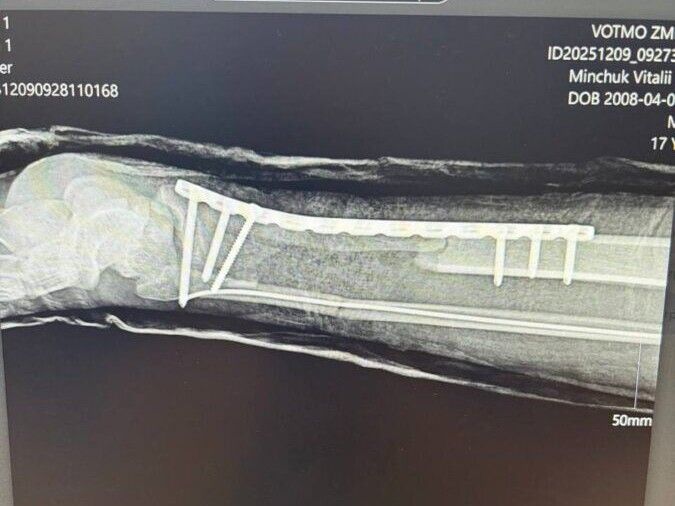

«Частина ноги трималася на шкірі, коли хлопця доправили до нашого медзакладу. Оскільки нога травмована внаслідок стискання, були великі дефекти кісток, м’язів, сухожилків, артерій: пошкоджено обидві судини, які кровопостачають ступню. На час доправлення хлопця до нашого медзакладу минуло понад 4,5 години після травми, тобто нога довго була без кровопостачання. Усі ці обставини ускладнювали ситуацію, незважаючи на які вдалося відновити життєздатність нижньої кінцівки», — розповів травматолог дитячий Ігор Тарасюк.

Після того, як пацієнт поступив у відділення невідкладної допомоги, пацієнта ургентно прооперували разом із судинними хірургами Волинської обласної клінічної лікарні Степаном Курачем та Сергієм Пісачуком. Також виконано складний металоостеосинтез.